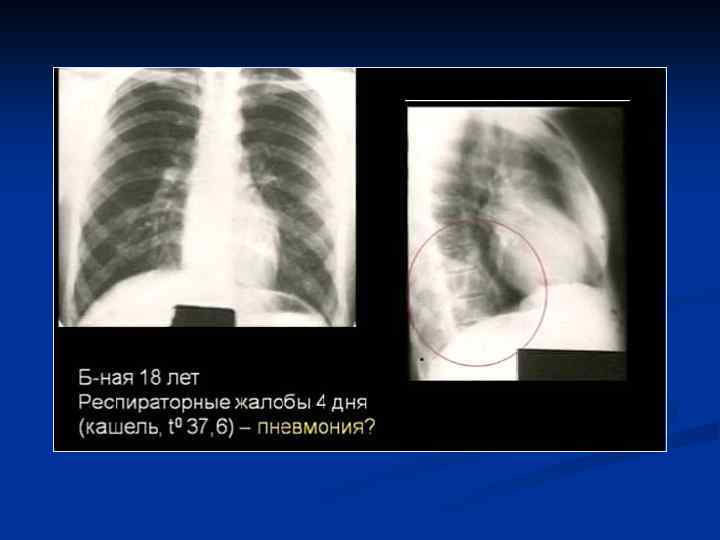

Клиническая картина Типичная - острое начало - лихорадка - кашель с обильной гнойной мокротой, влажные хрипы - боли в грудной клетке Атипичная - постепенное начало - сухой непродуктивный кашель - недомогание - першение в горле - миалгия - головные боли

ИТАК, n Долевые и очаговые инфильтративные изменения обычно характерны для бактериальных пневмоний n Сетчатые интерстициальные изменения или сочетание инфильтративных и интерстициальных изменений типичны для пневмоний вирусной, микоплазменной, хламидийной и пневмоцистной природы, а милиарные поражения — для туберкулеза легких, генерализованного сальмонеллеза, грибковых поражений. n Инфильтративные или интерстициальные изменения в сочетании с лимфоаденопатией типичны для туберкулеза легких и пневмоний, вызванных грибами, микоплазмой, хламидиями, вирусами кори и ветряной оспы.